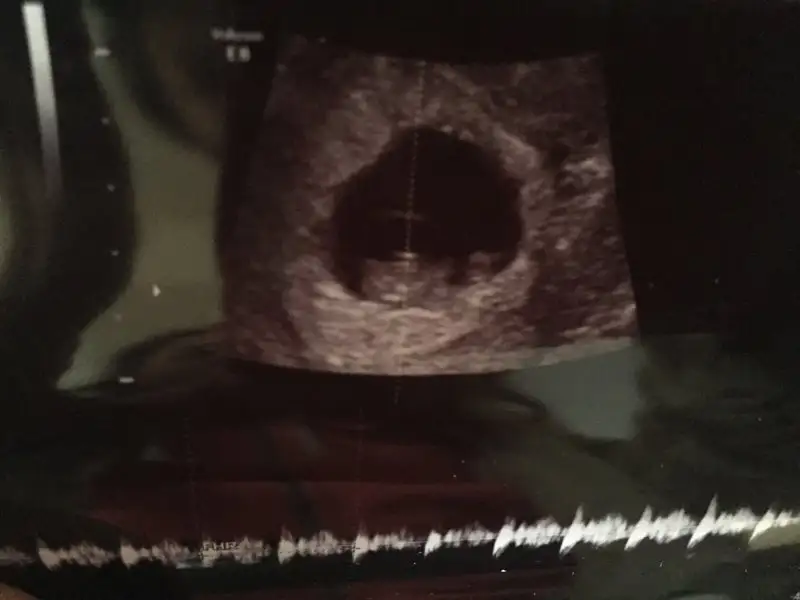

Kizlar benim mercimegimede yorum yapar misiniz???

Eklentiler

• IMG_20160121_114526.webp

IMG_20160121_114526.webp

7,9 KB · Görüntüleme: 68